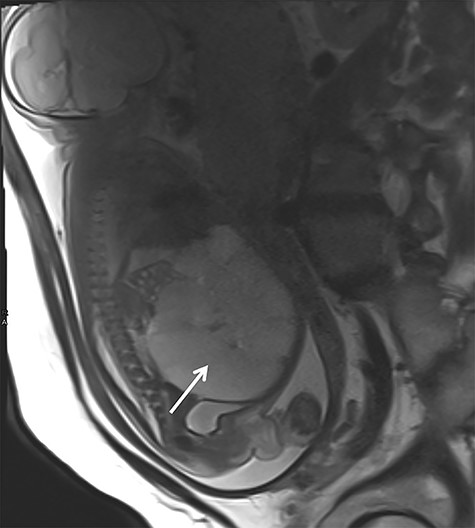

In the 18th week of gestation, routine ultrasound examination of a 35-year-old primigravida revealed a fetal cystic intra-abdominal mass occupying the entire abdominal cavity. A prenatal magnetic resonance imaging (MRI), performed in the 29th gestational week, showed a lymphatic cystic malformation measuring 12 × 7 × 9 cm (Fig. 1). In the 33rd gestational week, intestinal hypoperfusion due to compression by the malformation was suspected during an ultrasound examination. Therefore, a caesarean section was performed without complications.

Prenatal MRI in the 29th gestational week showing a multicystic septed mass occupying the complete abdominal cavity (white arrow).